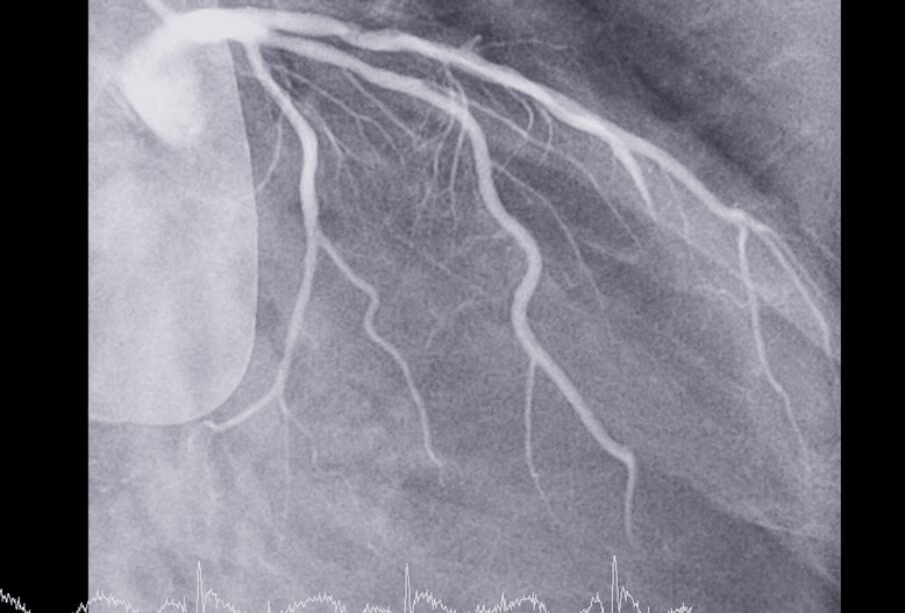

- Asinsvadu kateterizācija (angiogrāfija): caur cirksni vai kāju sirds asinsvados ievada plānu katetru un ievada kontrastvielu; pēc tam veiktā rentgenoloģiskā kontrole ļauj redzēt asinsvadu bojājumus vai nosprostojumus; šo izmeklējumu bieži veic pēc sirdslēkmes

Ārstniecības iestādēs miokarda infarktu diagnosticē, izmantojot vairākus izmeklējumus, tostarp asins rādītājus, attēldiagnostiku (rentgenogrāfiju, ehokardiogrāfiju, magnētisko rezonansi), EKG un angiogrāfiju. Būtisks sirds bojājums pēc simptomiem var līdzināties arī citām saslimšanām, piemēram, trauksmes lēkmēm vai plaušu embolijai, tādēļ precīzu diagnozi var apstiprināt tikai ārsts. Savlaicīga palīdzības meklēšana palielina iespēju saglabāt sirds veselību un mazināt nopietnu komplikāciju risku.